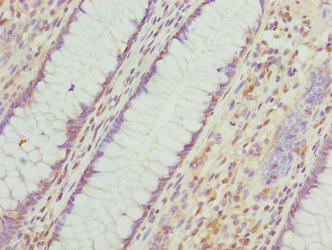

Immunohistochemistry of paraffin-embedded human colon cancer using CSB-PA847227LA01HU at dilution of 1:100